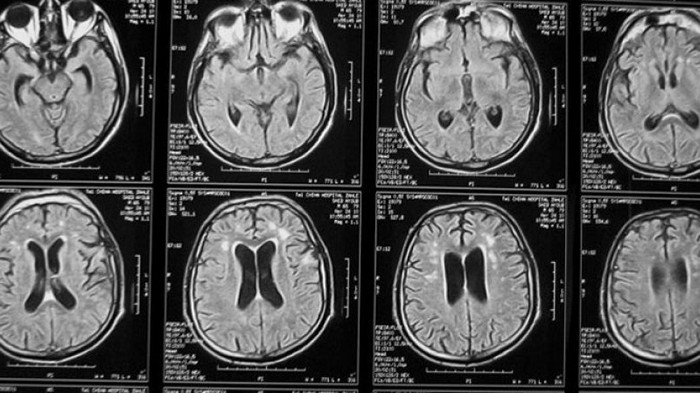

Американские ученые провели исследования, в ходе которых сканировали мозг молодых людей в возрасте 18–25 лет. Эти люди подвергались физическому, сексуальному насилию или издевательствам со стороны родителей. Результаты показали, что люди, которые в детстве страдали от словесных оскорблений со стороны сверстников, имели недоразвитые связи между правым и левым полушарием мозга, были более склонны к гневу, депрессии и тревоге.

При этом выяснилось, что именно оскорбления со стороны одноклассников имели наибольшее влияние. Исследования подтвердили, что «вербальное насилие» в подростковом возрасте провоцирует в дальнейшем серьезные отклонения. Например, тревогу, депрессию, гнев, враждебность, диссоциацию.